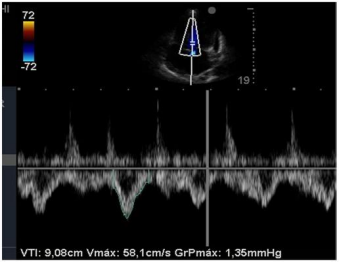

Insonação cardíaca Janela apical 5 câmaras com VTI de 9,08 cm

O nefrologista foi chamado a opinar na melhor conduta para o paciente. Para tanto, realizou uma ultrassonografia beira leito pulmonar e mensurou a velocidade integral tempo (VTI) do trato de saída do ventrículo esquerdo. Chegou, assim, à conclusão que poderia ser feita uma expansão no paciente. Com base nas imagens apresentadas, é correto afirmar que conduta recomendada pelo nefrologista está